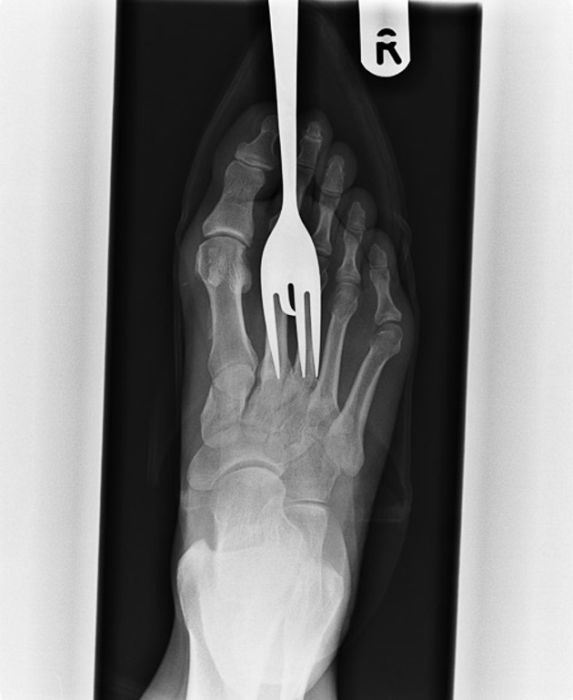

Рентгеновские снимки людей, которые умудрились сами или с чужой помощью разместить внутри своего организма разные посторонние предметы. От вилок и ножей до пуль и бензопилы (!!!). По этическим соображениям обычные снимки таких травм и повреждений выкладывать нельзя, зато рентгеновские можно – на них травмы видны достаточно условно, хоть и очень понятно.